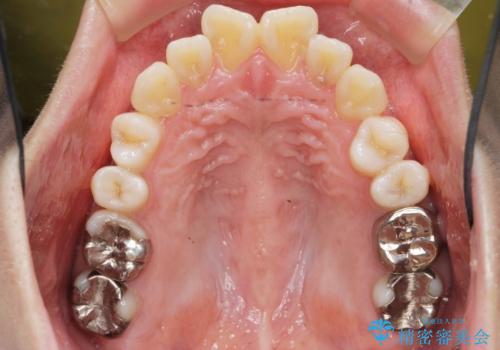

捻れた奥歯 突き出た前歯を治したい

- 出っ歯に見える前歯、捻れてしまった小臼歯の改善を求めて来院されました。

マウスピースでは改善の難しい小臼歯のねじれをまず部分ワイヤー矯正で改善し、その後マウスピース矯正で前歯の突出感を改善します。

時間はかかりましたが、捻れ、かみ合わせ、前歯の角度の改善が達成され満足いただくことができました。